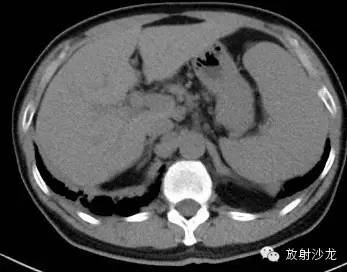

第三例:

51岁男性,体检发现肺门、纵隔、腹腔淋巴结肿大,CT拟诊结节病,后于北京协和医院确诊。

第1—3图显示Garland三联征。第4图显示腹腔淋巴结肿大。